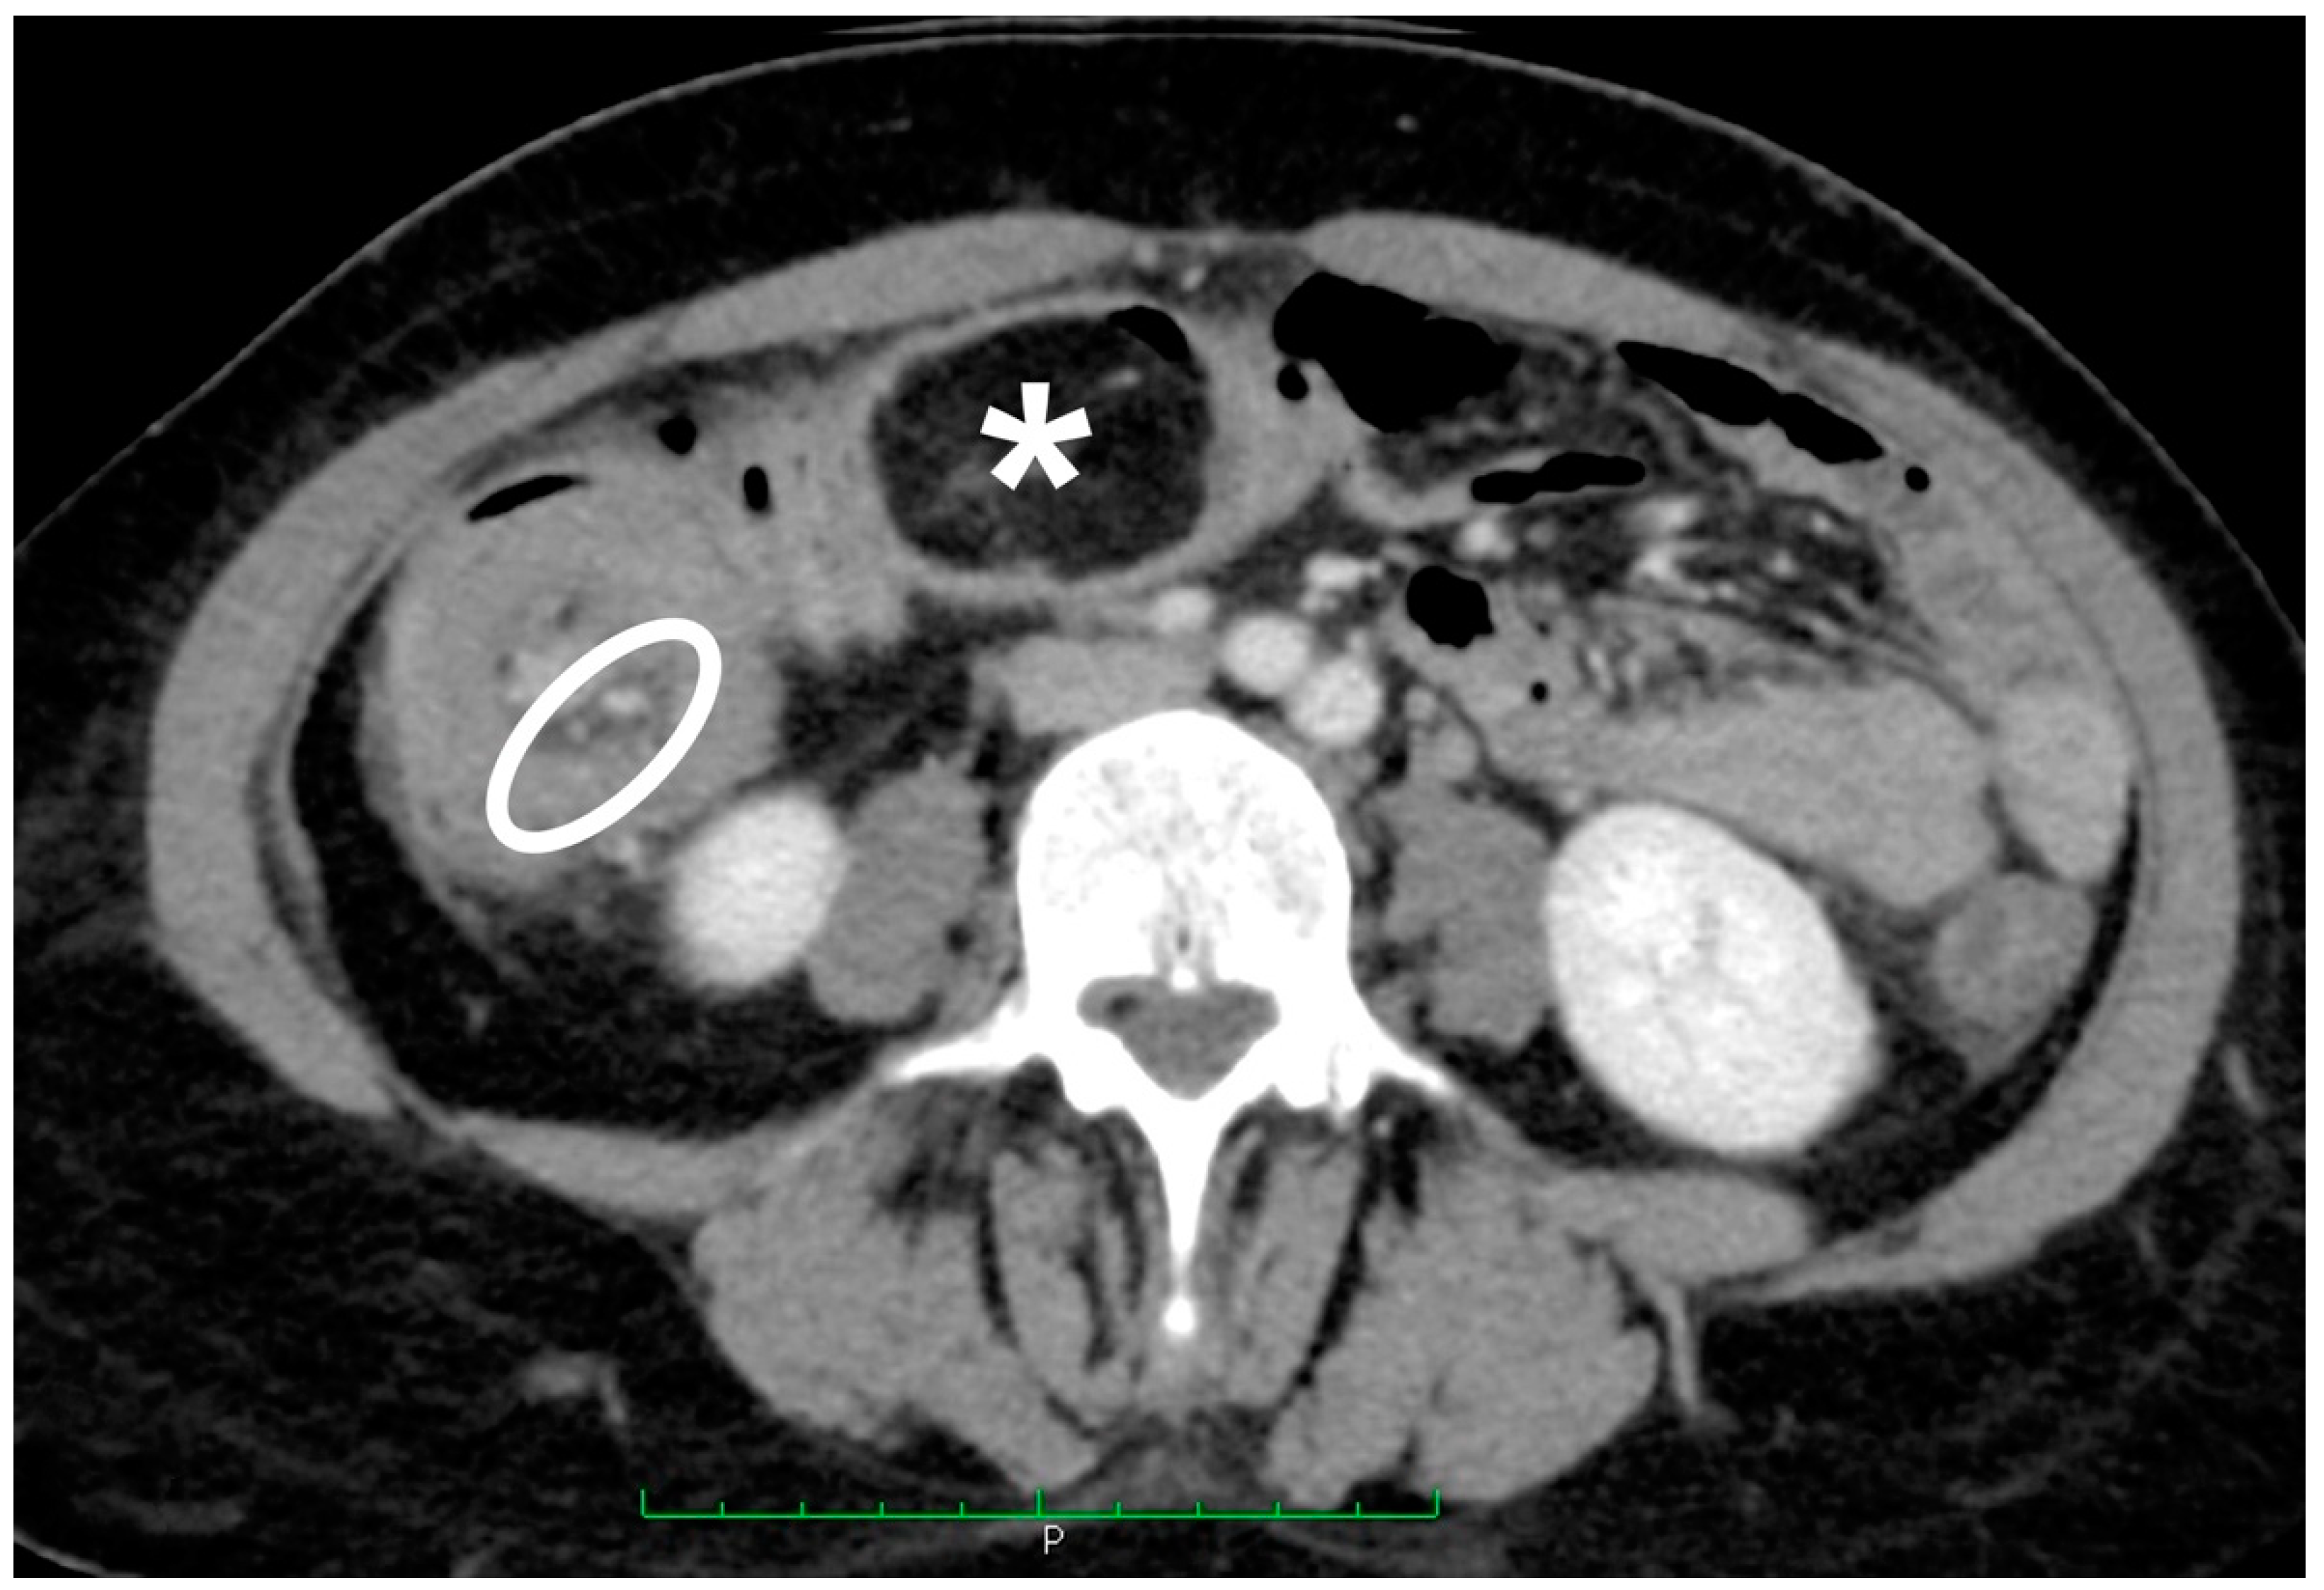

2. Materials and Methods

3.3. Instrumental Examinations